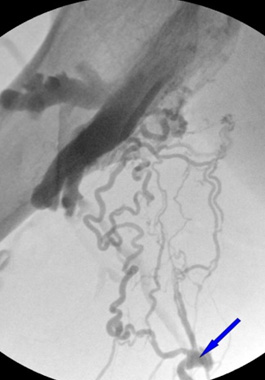

A thorough examination is required to clearly distinguish between muscle pain and varicose veins. In most hospitals, standard varicose vein tests focus mainly on the major veins, such as the great and small saphenous veins. However, exercise-induced varicose veins can also occur in smaller branch veins.If varicose veins in these small veins are overlooked and misdiagnosed as simple muscle pain, the optimal treatment window may be missed, limiting available treatment options.

At Sun Vascular Clinic, we carefully examine even the smallest branch veins to identify the root cause of the pain.